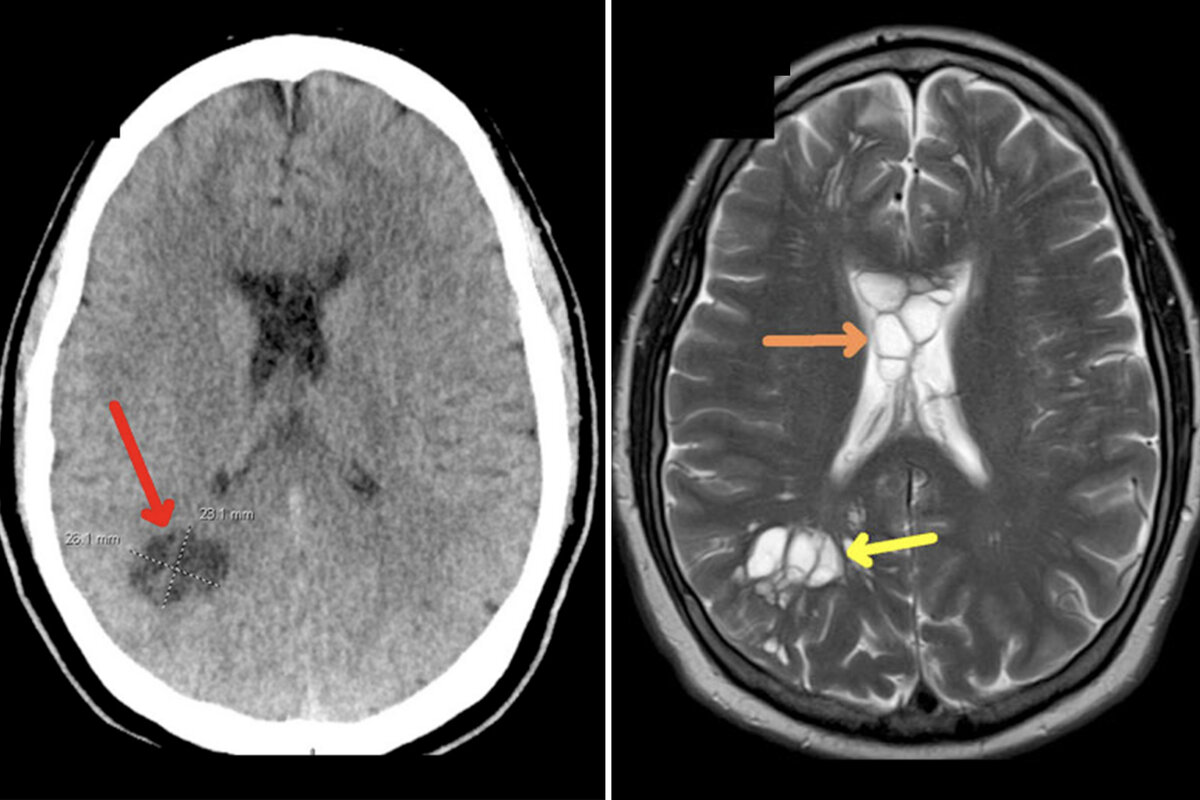

В данном случае, наряду с отеком, у пациента появились кисты по обе стороны мозга. Также было установлено, что ленточный червь успел отложить яйца в его мозге. Пациенту назначили дегельминтик альбендазол, что привело к улучшению состояния уже через две недели. Поскольку четыре из пяти случаев заражения такого вида паразитом сопровождаются припадками, медики предупреждают о необходимости "сохранять высокий индекс подозрительности и тщательно собирать анамнез у пациентов с изменениями в картине мигрени".